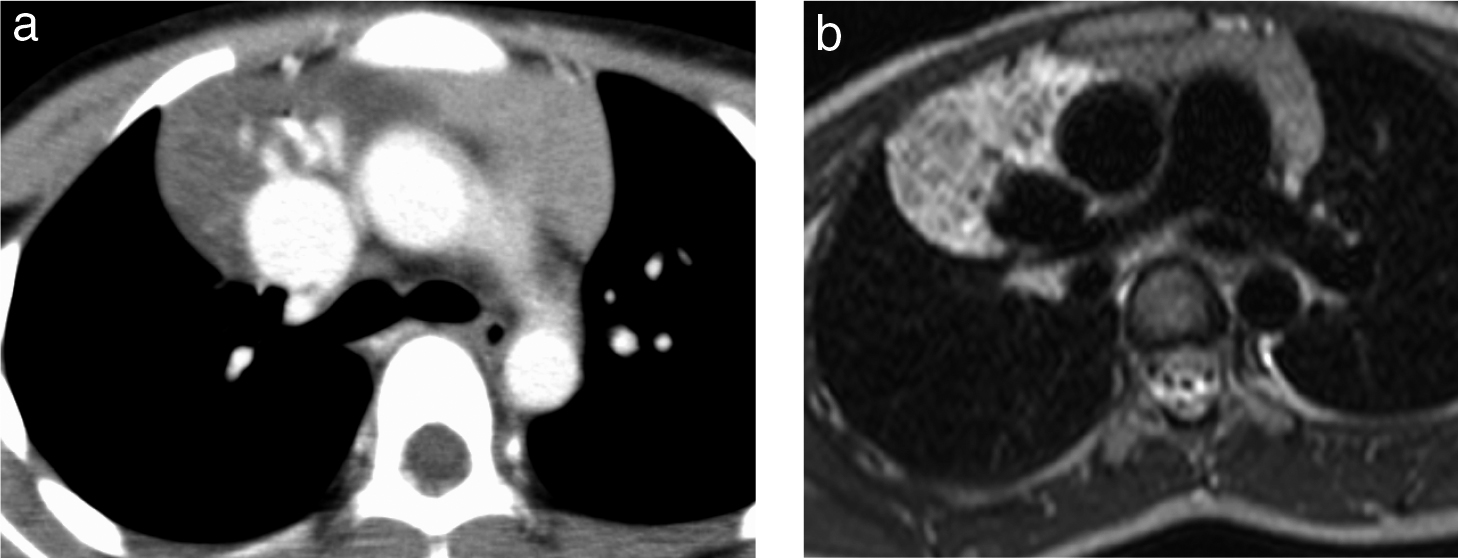

造影CTおよびMRI(8歳時)

造影CTでは前縦隔右側から心臓右縁にかけて44 × 32 mmの腫瘤を認め,胸腺に広く接しているが,境界は明瞭であった.腫瘤内にSVCに連続する拡張した異常血管構造を多数認めた(a).MRIではT1強調像で筋と同程度の中間信号,T2強調像で低~高信号が混在していた(b).

現病歴:8歳時に咳と発熱を主訴に近医を受診,胸部X線検査で右下肺野の浸潤影と縦隔側の腫瘤影を認めた(Fig. 1a).肺炎の診断で内服治療を行い,症状は改善したが,再検の胸部X線検査でも腫瘤影は残存していた(Fig. 1b).腫瘤性病変疑いで前医を紹介受診し,胸部computed tomography(以下CT)で前縦隔に腫瘤を認め,精査加療目的で当院を紹介入院した.血液検査では,異常は認めなかった.造影CTでは,前縦隔右側から心臓右縁にかけて44 × 32 mmの腫瘤を認め,石灰化はなく造影効果もなかった.胸腺に広く接しているが,境界は明瞭であった(Fig. 2a).腫瘤内に上大静脈(superior vena cava;以下SVC)に連続する拡張した異常血管構造を多数認めた(Fig. 2a)が,明らかな流入動脈は同定出来なかった.造影magnetic resonance imaging(以下MRI)ではT1強調像で筋と同程度の中間信号,T2強調像で低~高信号が混在していた(Fig. 2b).Dynamic studyではslow-persistent patternの増強効果(早期相で軽度の信号上昇を認め,遅延相にかけて漸増性に信号上昇する.良性腫瘍で主にみられるパターン.)を呈し,内部に拡張した血管構造があり,SVCと連続していた.T1強調像のopposed-phase(脂肪と脂肪以外の成分の信号が打ち消し合う相.少量の脂肪成分の検出に用いられる.)で脂肪成分を認めなかった.悪性疾患の否定目的で施行したpositron-emission tomography(以下PET-CT)では,FluoroDeoxyGlucoseの異常集積を認めなかった.摘出術を想定した場合,流出入血管を同定・把握しておく事は不可欠であり,診断的意味を含めて血管造影を行った.血管造影では,右内胸動脈から分岐する血管が腫瘤に流入しており(Fig. 3a),SVCに還流する異常血管を認める(Fig. 3b)が,逆行性造影では腫瘤内部は造影されなかった.以上の結果から,胸腺腫や奇形腫としては非典型的であり,血管腫などの間葉系良性腫瘍や肺葉外肺分画症を鑑別に挙げ,無症状であることから,経過観察の方針とした.